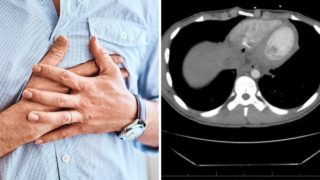

Negli Usa, un 17enne si è recato in un ospedale perché da giorni soffriva di forti dolori al petto: è così che i medici hanno scoperto che il giovane aveva un ago conficcato nel cuore. L’incredibile vicenda è diventata oggetto di un “case report”, pubblicato sul The Journal of Emergency Medicine. Secondo quanto ricostruito, il 17enne si è recato al pronto soccorso del Memorial Medical Center in Massachusetts a causa di fori dolori al petto che non passavano e che anzi aumentavano nel momento in cui il ragazzo era in posizione sdraiata o quando respirava profondamente. I medici in un primo momento hanno pensato a un’infiammazione del muscolo cardiaco, ma poi la Tac ha mostrato un “oggetto estraneo metallico lineare”, lungo circa 3,5 centimetri, che sporgeva dal ventricolo destro.

Quando i dottori gli hanno chiesto se avesse ingoiato oggetti estranei o subito traumi al petto, il giovane ha inizialmente negato, ma successivamente ha raccontato che, poiché lavora in una sartoria, spesso tiene degli aghi in bocca mentre cuce vestiti su misura. Il 17enne, dunque, deve aver ingerito uno spillo senza neanche accorgersene. La conferma è arrivata quando i medici, che lo hanno operato a cuore aperto, hanno potuto constatare che il corpo estraneo conficcato nel cuore dell’adolescente era effettivamente un ago. Secondo i dottori è possibile che l’ago si sia spostato dallo stomaco al cuore, ma non è escluso che il suo percorso possa essere stato anche diversi, passando ad esempio per l’esofago. L’intervento, comunque, è perfettamente riuscito e ora il giovane si è ripreso senza aver subito conseguenze.